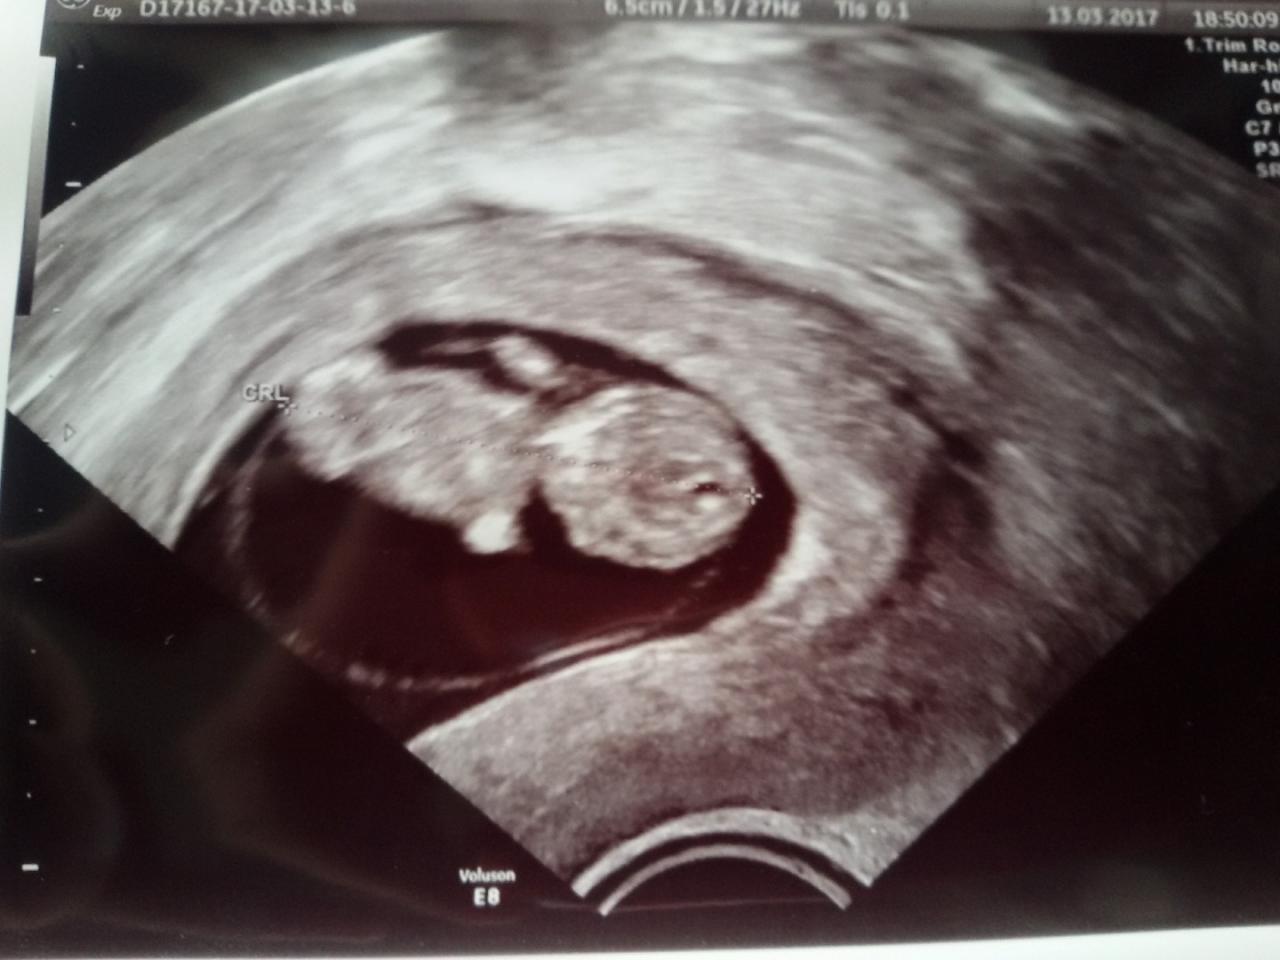

Ja jestem po wczorajszej wizycie i usg. Wyniki są ok. Siedziałam tam40min.Zobacz załącznik 798745 Teraz tylko na testy Pappa i Nifty. Oby bylo dobrze.